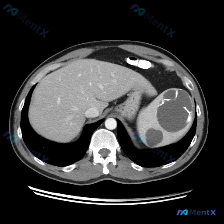

今天整理了一个很有警示意义的腹部CT病例,先看影像表现,再聊我的分析思路。 先看影像核心发现 这是一份腹部CT轴位图像: - 肝脏:实质密度均匀,血管走行正常,未见局灶性占位。 - 脾脏:形态异常,脾实质内见多发、大小不等的囊性病灶,呈圆形/类圆形,边界清晰;最大病灶位于脾中部,囊壁可见明显的环形/...